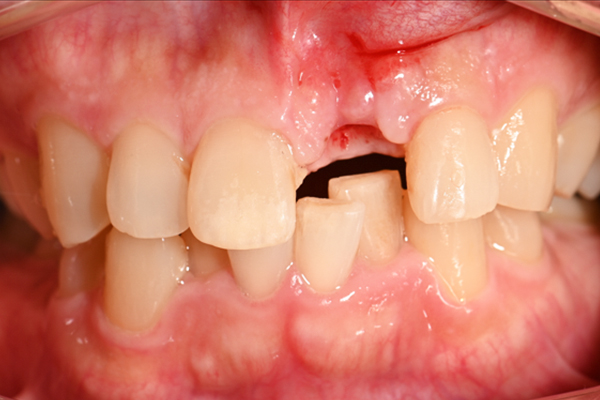

| 主訴 | 前歯が揺れる |

|---|---|

| 治療内容 | 上の前歯のインプラント治療 |

| 治療期間 | 4ヶ月 |

| 治療費 | 39万7千円 |

| 治療 リスク | インプラントの土台を入れた後最終的な歯が装着されるまで仮歯をしていただきます |